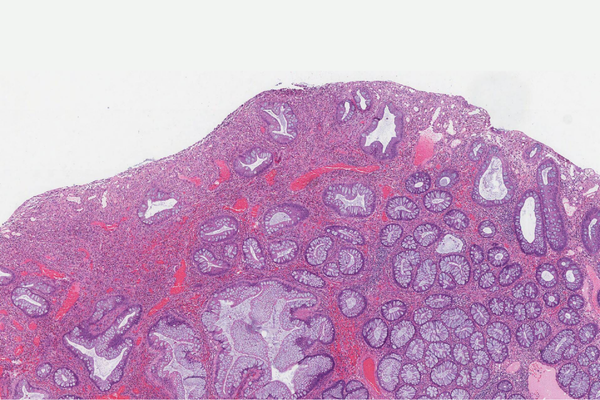

Adenomatous Polyps (Precancerous Polyps)

These are the most common type of polyps and can develop into cancer if not removed. Polypectomy helps in preventing colorectal cancer.